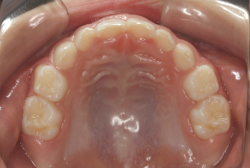

凸凹な歯並びのことを叢生といいます。矯正歯科に来院する患者様の主訴の中で、最も多いのが「配列の凸凹を真っ直ぐにしたい」というものです。歯の大きさと顎の大きさの調和がとれていないことが原因です。

凸凹を主体としたケースの場合、当院の平均治療期間は18ヶ月ですので、このケースは少し長めに経過しました。理由の一つは凸凹の程度がかなり重症だったと言うことですが、もう一つは、右下第2大臼歯が45度くらい前傾していたため、それを整直化させるために時間を要したと考えています。いずれにしても最終結果は大変よい状態と思います。

治療前は並びが乱れて見た目が悪いというのはもちろん問題ですが、歯科医学的に一番困るのは噛み合わせが悪いという点です。上下の犬歯(3番目の歯)は、上下的に離れた位置にあるため接触することができません。つまり歯としては存在していても、歯としては機能していないということです。